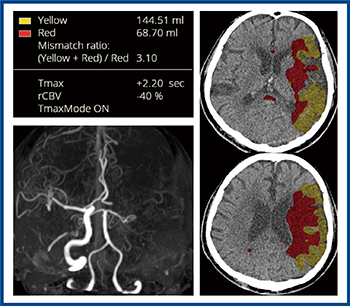

造影CTの解析を行うBrain Perfusion(図2 a)は,ベイズ推定を用いたデコンボリューション法による脳灌流解析で,各種マップ画像を並べて表示し,一元的な評価が可能となる。また,Brain Vessel Occlusionは,血管が表示されない領域を抽出し,閉塞血管の強調画像を作成・表示する(図2 b)。

図2 Abierto RSS for Neuroの造影CT解析のアプリケーション

頭部単純CTでは出血を認めず,Abierto RSSでは脳の左半球の早期虚血性変化が表示された(図3)。急性期脳梗塞疑いにてperfusion CTを施行し,Abierto RSSにて自動解析が行われた。結果画像は自動でPACSに転送されるため,操作室で診療放射線技師が,各種マップ画像や4D画像にて閉塞血管などを一元的に確認すると同時に,救急外来では主治医が適応判断を行い,カテーテル室では治療の準備を進めることができる。図4はAbierto RSSの解析結果であるが,虚血コア体積は68.7mLとやや大きいものの,ペナンブラ領域も広汎に認め,また,mismatch ratioは3.1であり,血栓回収療法の適応と判断した。

図4 Perfusion CTの解析結果

■:虚血コア領域 ■:ペナンブラ領域